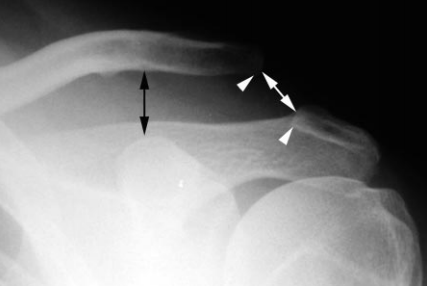

Grade IV

- Grade III avec déplacement postéireur de la clavicule dans le muscle trapèze

Grade V

- Grade III exagerée

- Distance CC > 25mm